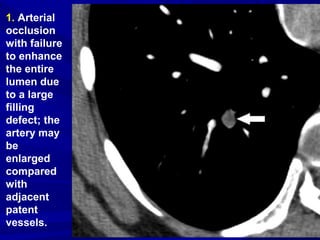

1. Arterial

occlusion

with failure

to enhance

the entire

lumen due

to a large

filling

defect; the

artery may

be

enlarged

compared

with

adjacent

patent

vessels.